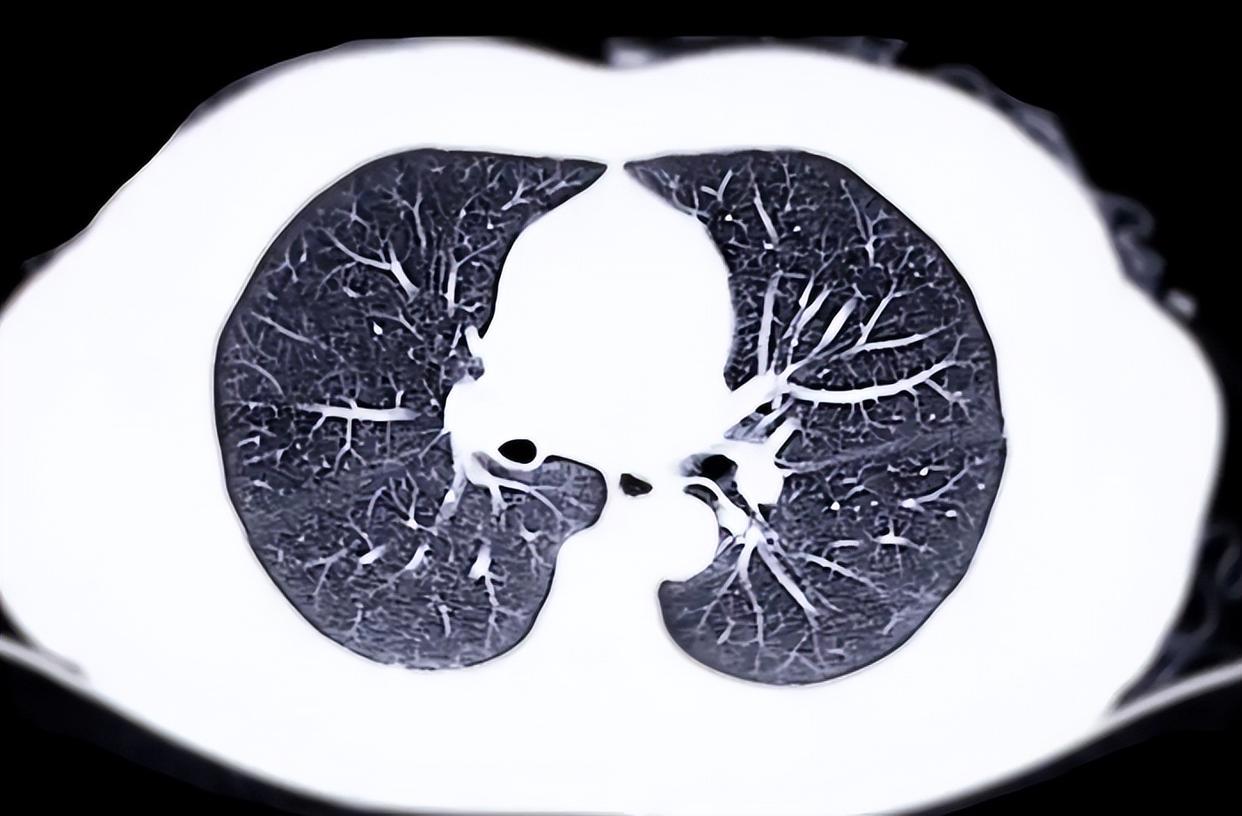

而肺部CT报告中的某些描述,比如“磨玻璃影”“微小结节”“间质性改变”,对普通人来说如同天书,却可能是医生判断肺健康的重要线索。这些术语到底意味着什么?是不是一看到就得立刻紧张?

先别慌。医学界普遍认为,多数肺部微小结节是良性的,尤其直径小于6毫米的,随访观察即可。真正需要关注的是那些形态不规则、边界模糊、或短期内快速增大的病灶。

某三甲医院呼吸科医生曾提醒:“我们不怕发现结节,怕的是忽视变化。”可问题来了——既然很多结节无害,那我们该如何分辨哪些需要干预,哪些只需安心等待?

说到就医,很多人一听到“做CT”就害怕辐射。低剂量肺部CT的辐射量极低,相当于乘坐几小时飞机所受的自然本底辐射。对于40岁以上、有吸烟史、家族肺癌史或长期接触有害环境的人群,定期筛查反而是一种保护。

那么建议咨询专业医生是否需定期肺部筛查。但即便不属于高危,若体检发现异常描述,也应遵医嘱随访。随访不是“等它变坏”,而是动态观察,把握最佳干预窗口。